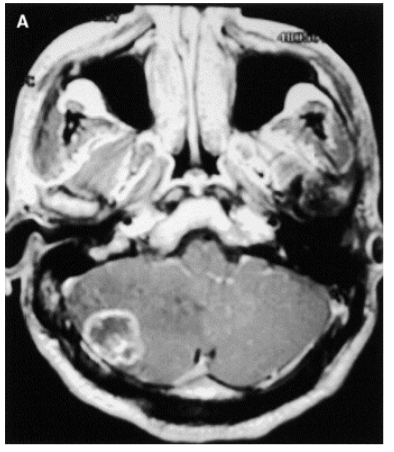

Considere um paciente masculino 55 anos com historia de hemiparesia direita há 2 semanas, sem nenhum fato significante de antecedente.

De acordo com a imagem acima, dentre os diagnósticos abaixo descritos, qual o mais provável?